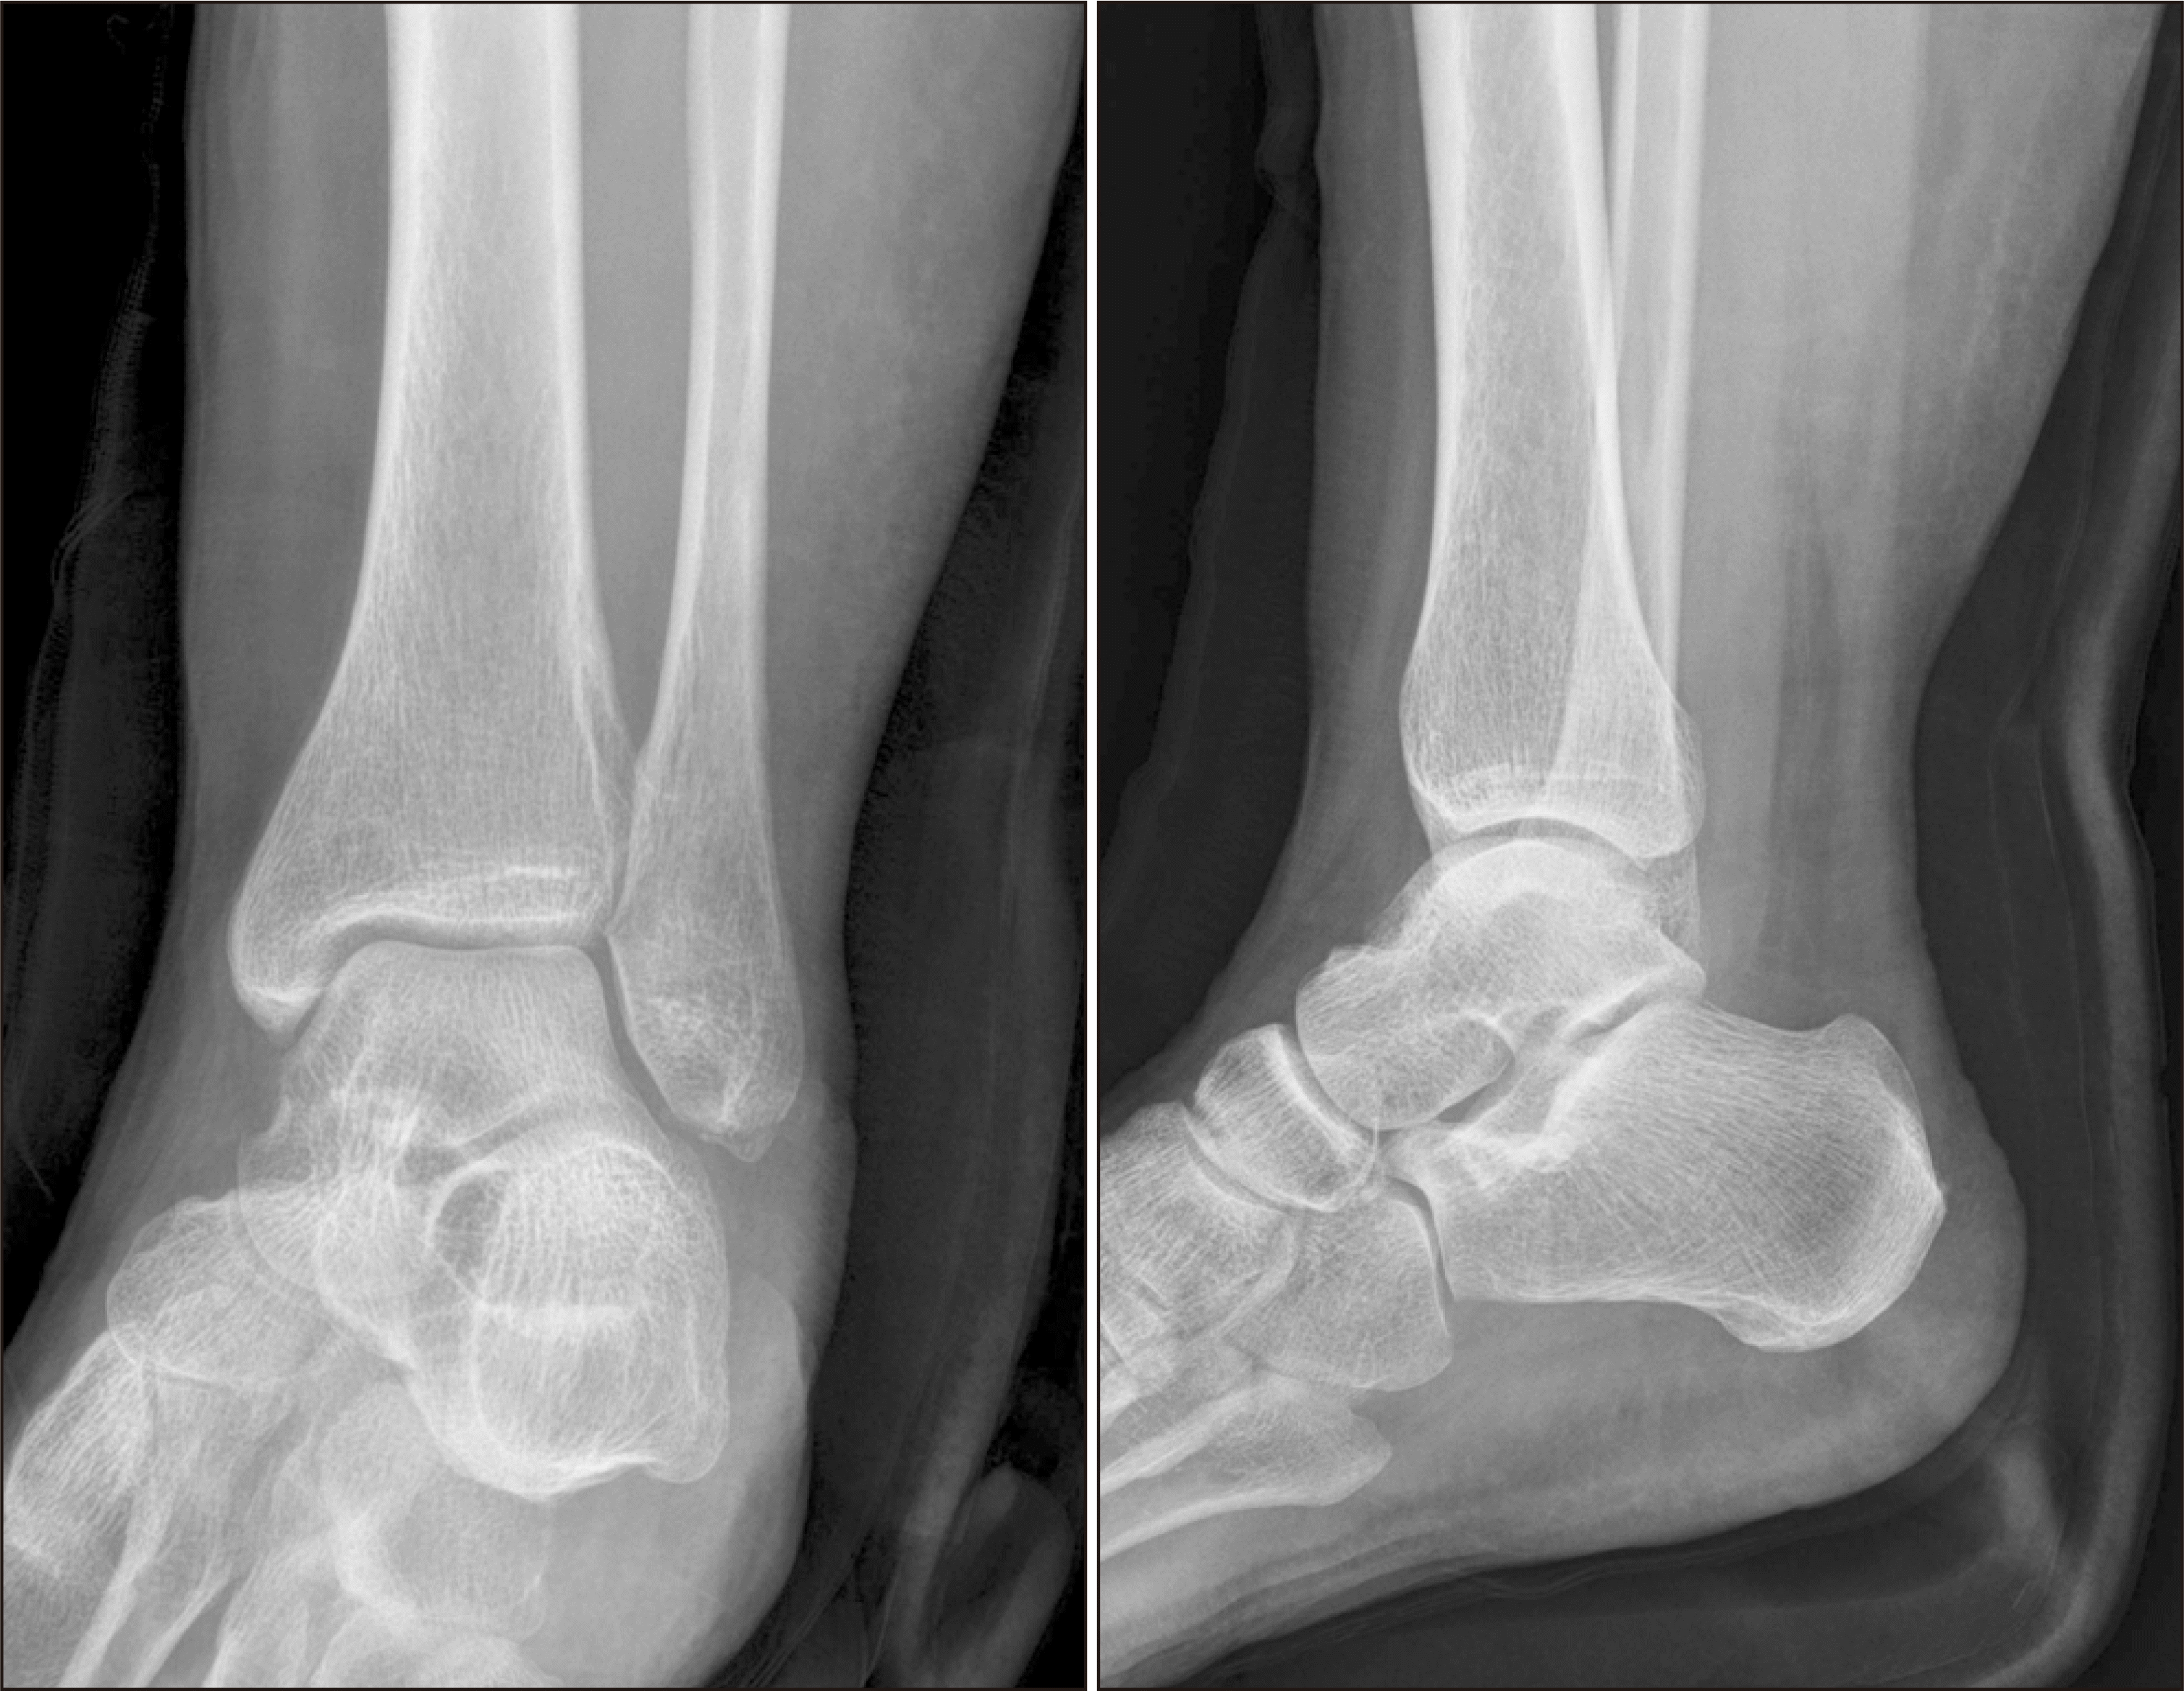

Figure 1

Simple radiographs of the left ankle show an avulsion fracture of the lateral malleolus (arrow).